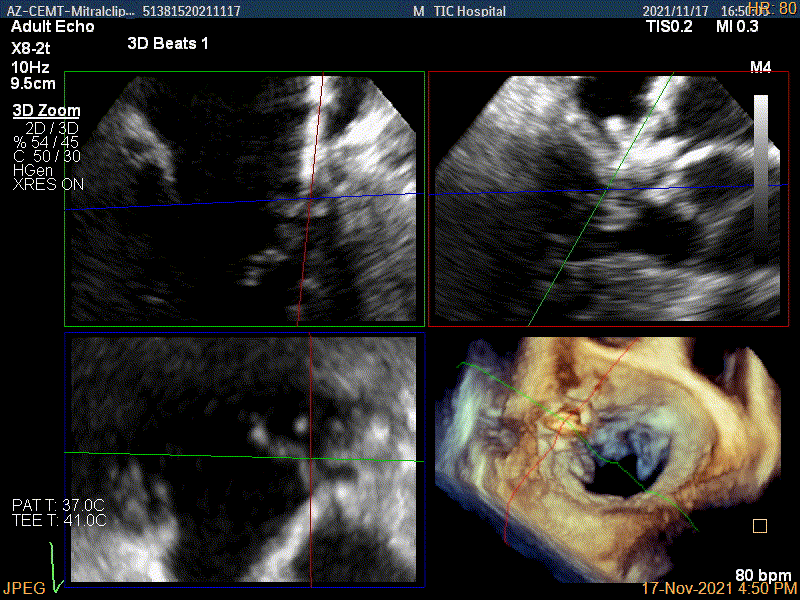

术前超声评估结果

术前超声诊断

3D-color MV view:源自于交界区的大量反流

Qlab软件勾画估测瓣口面积约:6.52cm²